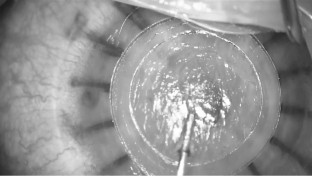

Liu YC, Wittwer VV, Yusoff NZM, Lwin CN, Seah XY, Mehta JS, et al. Intraoperative optical coherence tomography-guided femtosecond laser-assisted deep anterior lamellar keratoplasty. Cornea. 2019;38:648–53.

Abusayf MM, Liu YC, Han E, Yu ILX, Riau AK, Mehta JS. One-step intraoperative optical coherence tomography guided tunnel, mushroom femtosecond laser big bubble deep anterior lamellar keratoplasty. Bioengineering, 2024;11:639.